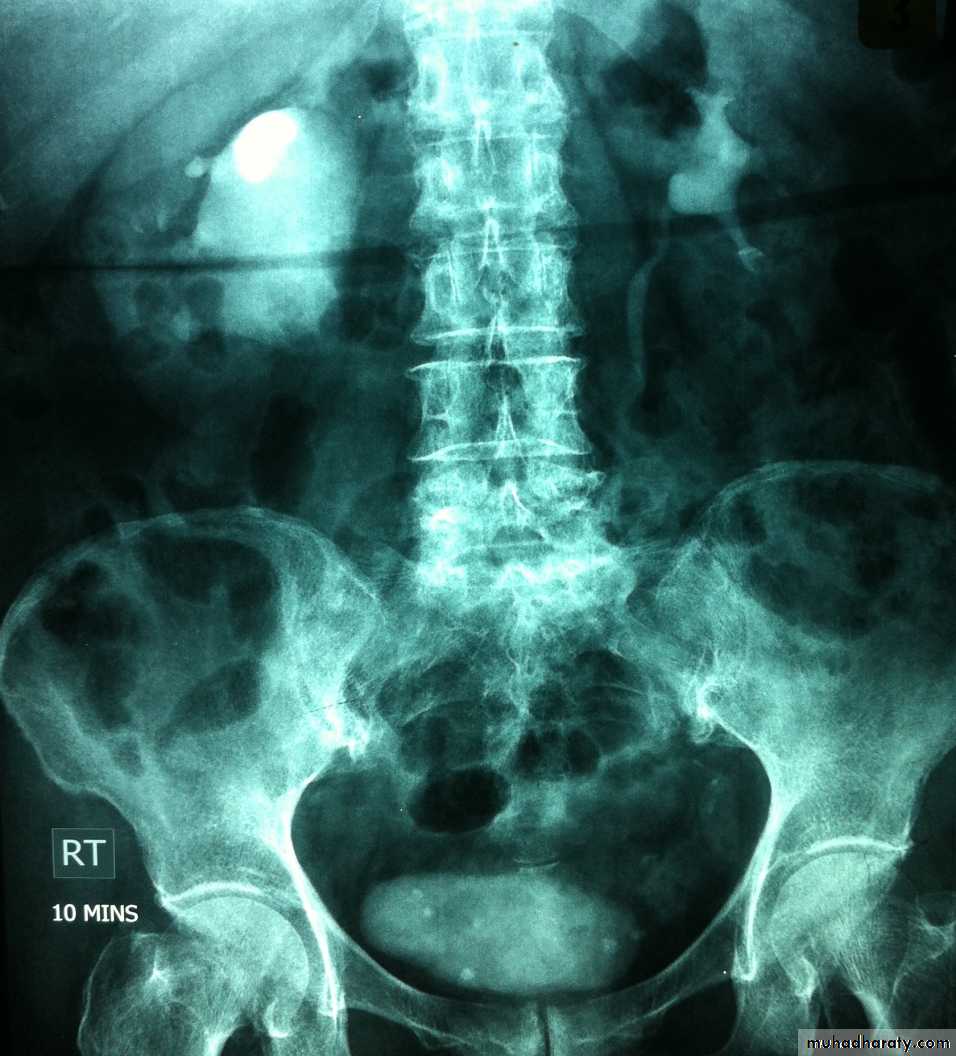

36- Hydronephrosis